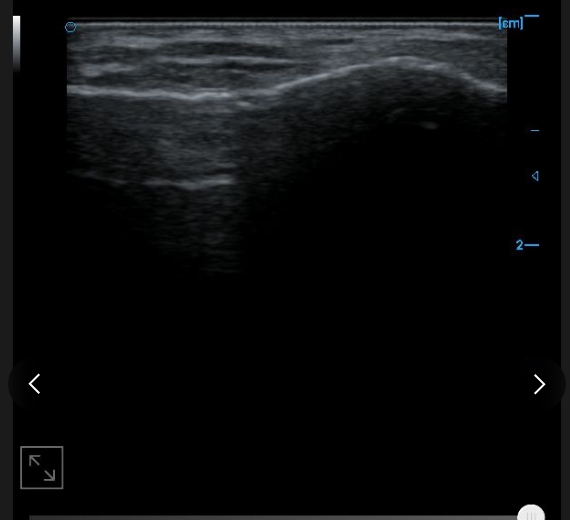

Internal testing supports images with B

External testing supports images with B

Posterior tibial tendon B image

Posterior calcaneal bursa B image